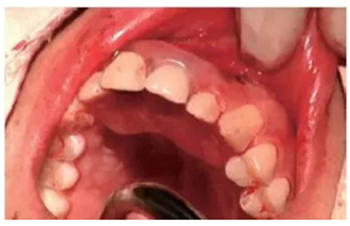

從圖1可以看出患者缺牙區(qū)的間隙充足,牙齦健康,頰側(cè)軟組織略有凹陷。

圖1 缺牙區(qū)的頰側(cè)和口內(nèi)照片